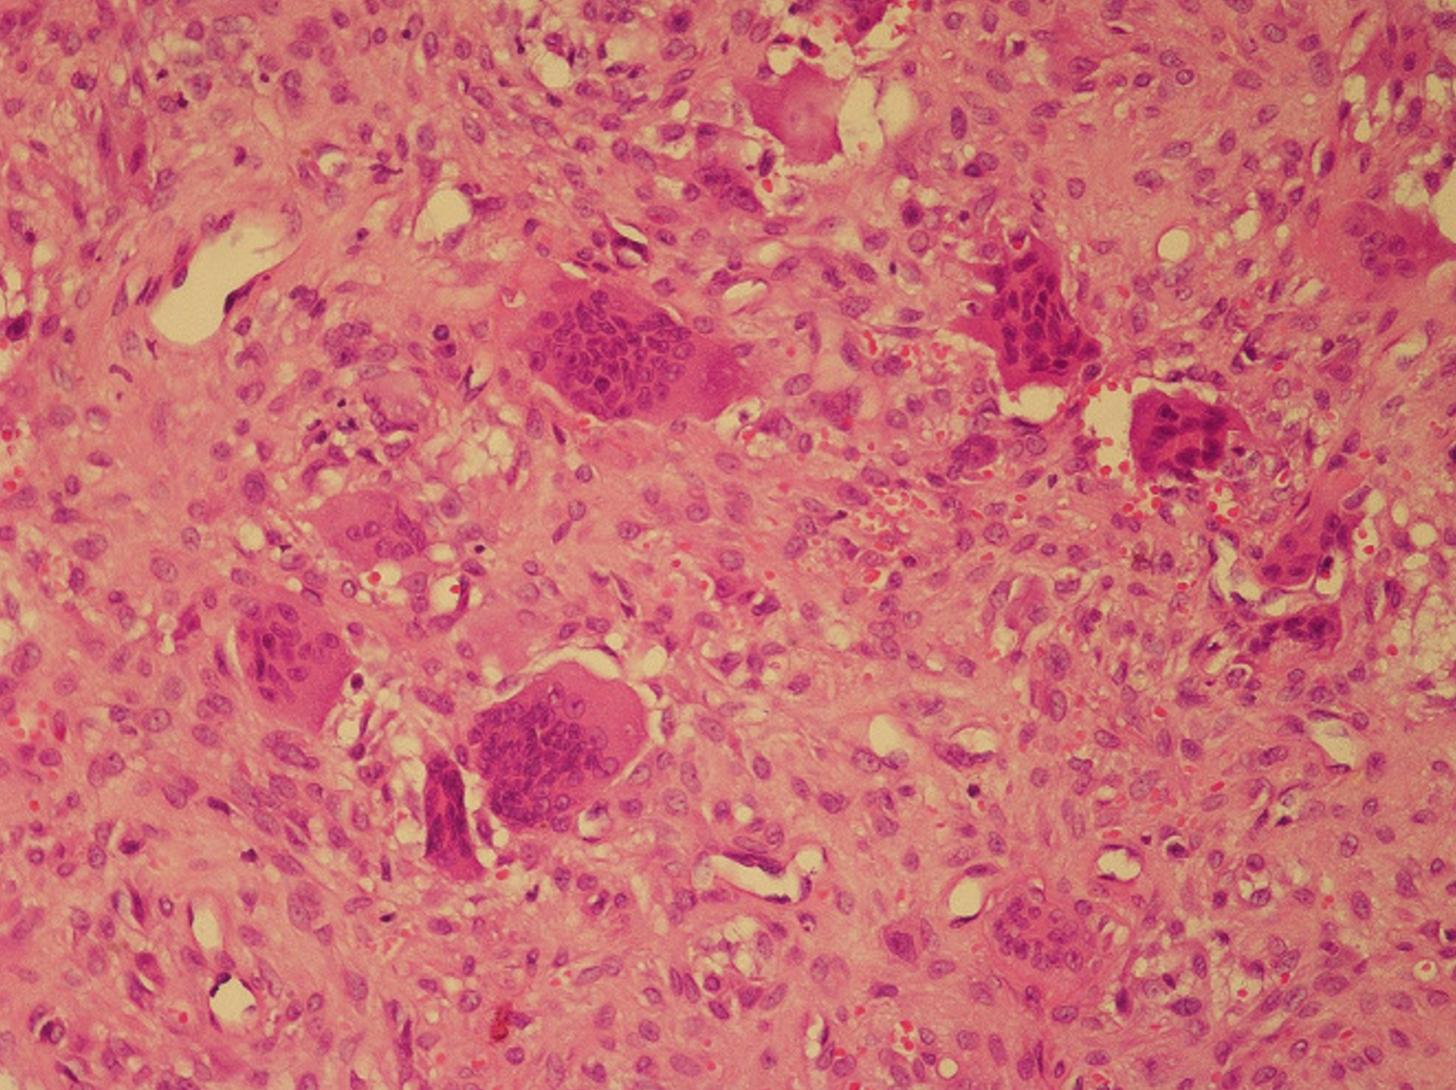

通过开颅手术切除了病变。手术过程中观察到肿块附近的硬脑膜完好。术后没有出现重大并发症。组织病理学检查标本支持BT的诊断,纤维骨病变包含巨细胞并伴有骨吸收。光学显微镜显示血管增加、成纤维细胞增殖、含有渗出红细胞的基质和破骨细胞型巨细胞(图4)。

图4 该图像显示了在光学显微镜下对肿瘤进行的病理检查